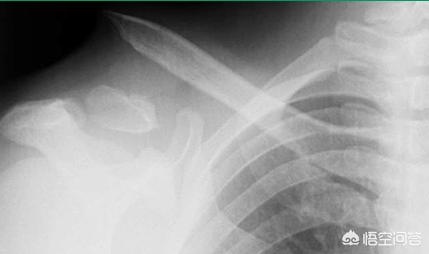

但注意:对于伴有锁骨周围韧带损伤,失去韧带保护的锁骨骨折来说,避免使用“8”字绷带固定法,因为不能支撑手臂的重量,有可能会加重骨折移位,需要大家注意!(如下图)

宝宝骨折保守治疗跟手术治疗,为什么儿童骨折医生建议保守治疗